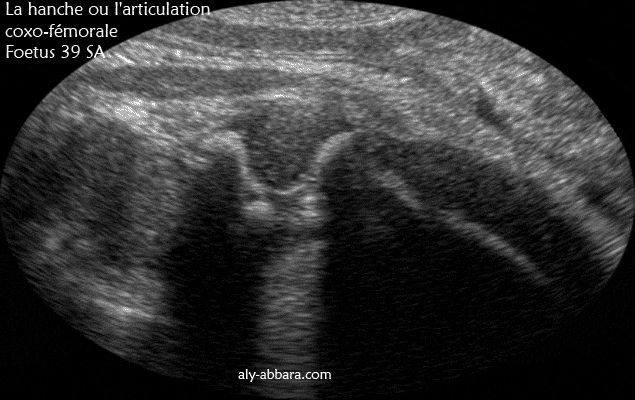

Image échographique montrant les éléments anatomiques composant la hanche ou l'articulation coxo-fémurale (la tête de la fémur et la cavité de l'acétabulum "acétabule").

Fœtus de 39 SA d'âge.